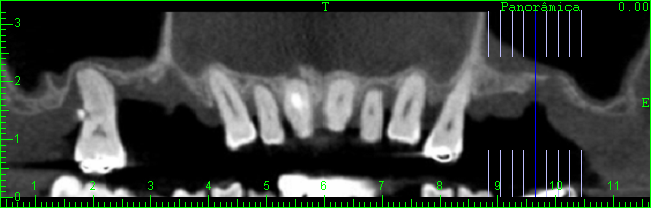

TOMOGRAFIA COMPUTADORIZADA ANTES DO ENXERTO ÓSSEO